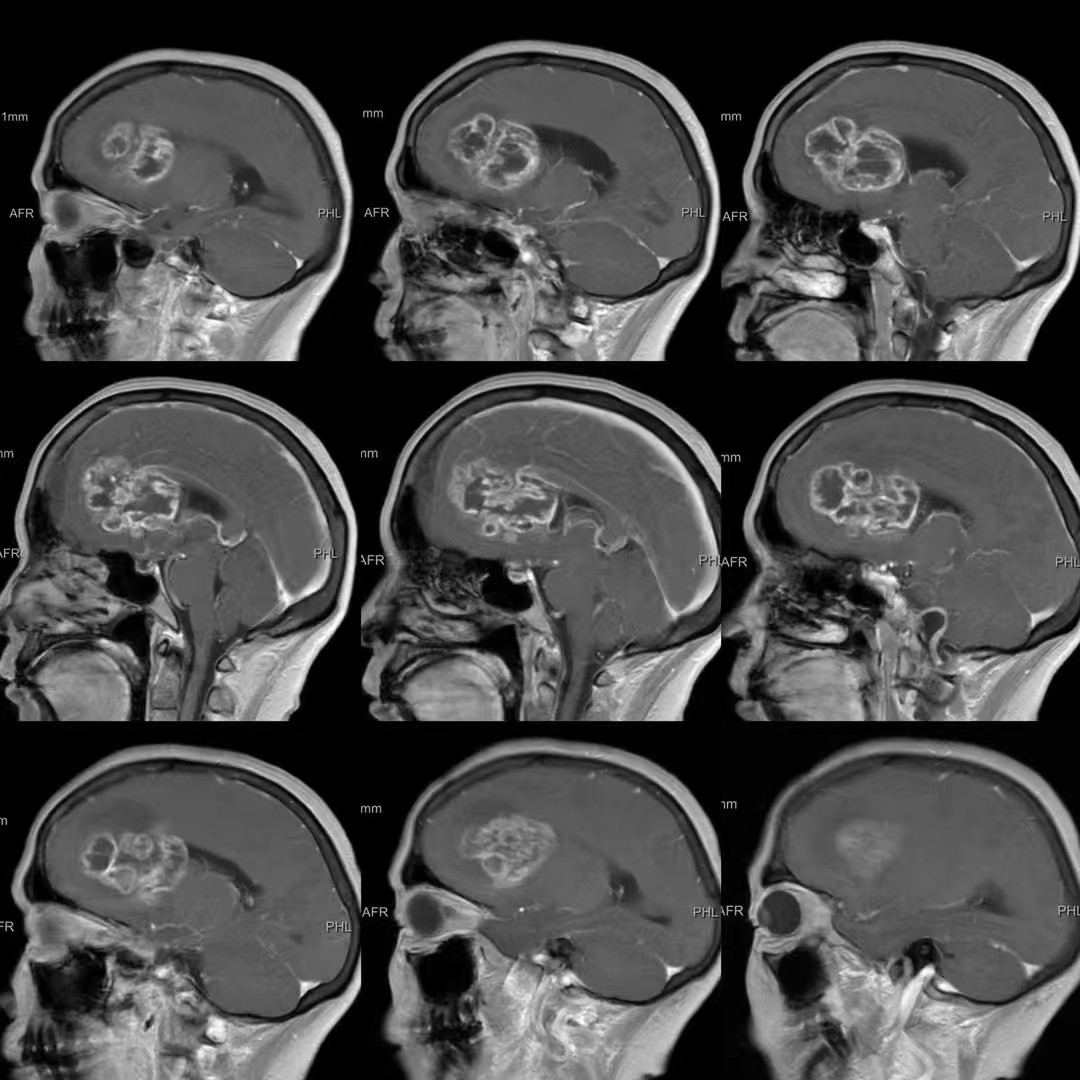

患者,女性,58岁,因“反应迟钝、记忆力下降1月,加重伴头痛、恶心、呕吐1周”入院。

巨大蝴蝶型胶质母细胞瘤(Butterfly glioblastomas)切除术